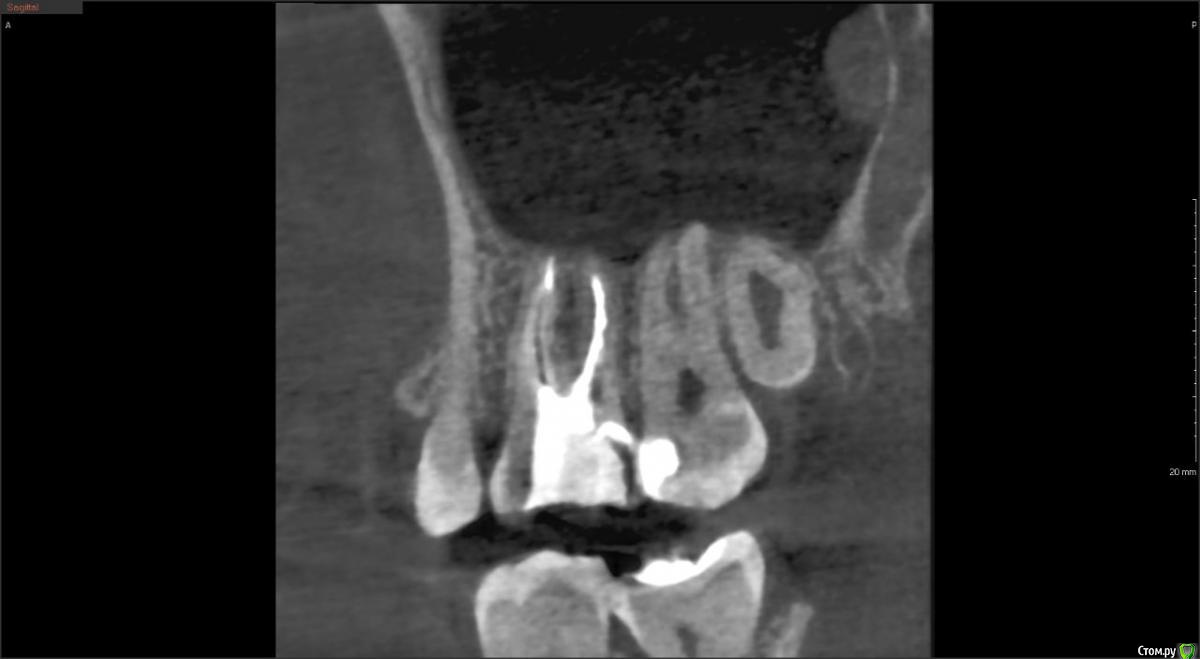

red_butler Опубликовано 4 февраля, 2020 Поделиться Опубликовано 4 февраля, 2020 Покажите ещё срезы Кт Ссылка на комментарий

Liza544 Опубликовано 4 февраля, 2020 Автор Поделиться Опубликовано 4 февраля, 2020 Вот еще пару снимков которые у меня есть. ПРошу заметить, что последние 4 снимка (файлы 7-10), которые я тут прикрепила - до пломбы на 25-м зубе и до залеченного 4-го канала в 26-м зубе. Подскажите пожалуйста, может ли быть зуб недостаточно залечен, хотя на КТ ничего подозрительного не видно? Ссылка на комментарий

ЛанаМ Опубликовано 4 февраля, 2020 Поделиться Опубликовано 4 февраля, 2020 Воспаление десны может давать постоянные ноющие боли и боль при накусывании. От чистки сразу не пройдет, нужно дней 5-7 противоспалительного лечения и отсутствие травмирования (постараться ниткой не чистить). Также нужно убедиться, что нет хронического воспаления в гайморовой пазухе. Побольше срезов кт, желательно уже после пломбирования четвертого канала. Да, бывают проблемы в зубе и при идеальной картинке рентгеновского снимка. На нем видны только крупные каналы, а там еще целая сеть мелких. Ссылка на комментарий